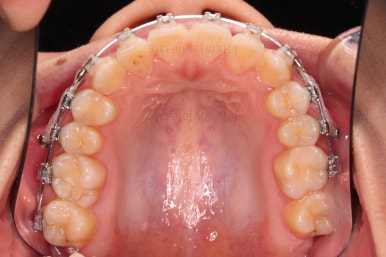

치열의 고른 느낌 좋고요.

덧니, 교합, 중앙선 등 모든게 좋아졌네요.

부산치아교정치과 전후 비교해 보겠습니다.

교합, 맞물림, 중앙선, 덧니, 입매, 앞니위치 및 각도 모든게 잘 마무리 되었습니다.

비발치로 오히려 입이 들어가게(악궁확장이나 치간삭제(공간확보의 목적) 없이도) 할 수 있었던 부산치아교정치과 좋은 치료였습니다.